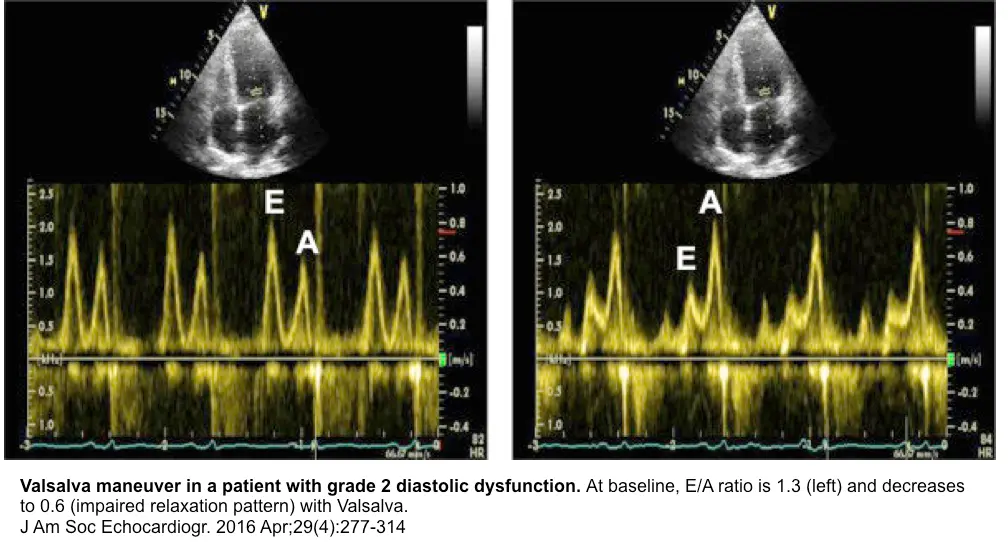

- Valsalva maneuver to tease out normal vs “pseudonormal” (grade II) diastolic dysfunction

- tbh, this is an old school 👵 approach, so you may rarely have a sonographer collect this for you

- normal: Valsalva → ↓ preload → ↓ amplitude of both the E- and A-wave

- grade II diastolic dysfunction: Valsalva → ↓ preload → filling will occur on the flatter portion of the LV diastolic PV relationship; ∴, E-wave amplitude ↓ > A-wave amplitude ↓ less (or may actually ↑) → E/A reversal (i.e., E/A ratio <1)